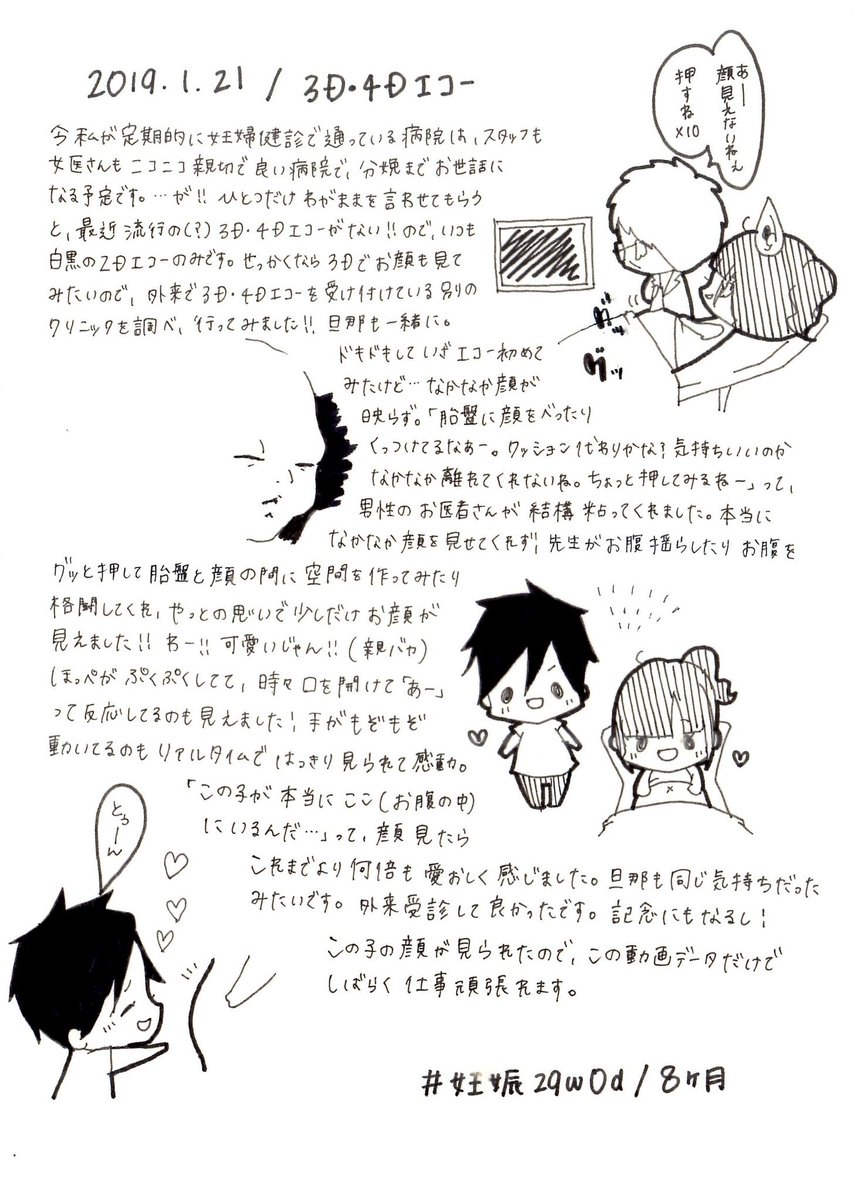

2019.1.21 初の3D&4Dエコー! お顔が見られたのがすごく嬉しかったし、これまで以上に愛おしく思えました! 次の子産むまでに、うちの産院にも3D4Dエコー導入されないかな? #育児漫画 #育児日記 #妊娠 #妊娠後期 #妊娠8ヶ月 #エコー #ママ垢さんと繋がりたい #絵描きさんと繫がりたい pic.twitter.com/95iafDyuae

2019-08-31 19:25:17 拡大

拡大

拡大

拡大